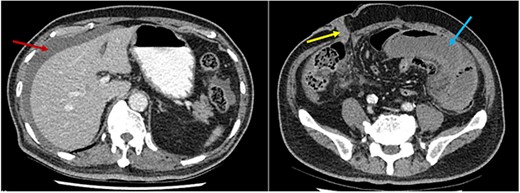

A 75-year-old male presented to our institution 4 months after RC for bladder cancer with acute abdominal pain and vomiting. Vital signs were within normal limits, the abdomen was distended and tender in the left lower quadrant. Significant biochemical derangements with metabolic acidosis and elevated lactate were demonstrated. A computed tomography (CT) scan of the abdomen and pelvis demonstrated a closed-loop SBO in the left lower quadrant with intrabdominal free fluid (Fig. 1). The right-sided ileal conduit appeared healthy.

CT scan axial slices demonstrating perihepatic free fluid (red arrow) and dilated loops of small bowel in the left iliac fossa (blue arrow). The ileal conduit (yellow arrow) in the right iliac fossa appears healthy.